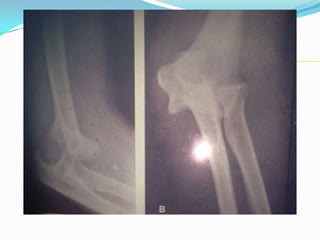

La rayos X AP y lateral es

imperativa para confirmar

el diagnóstico y descartar

fracturas asociadas